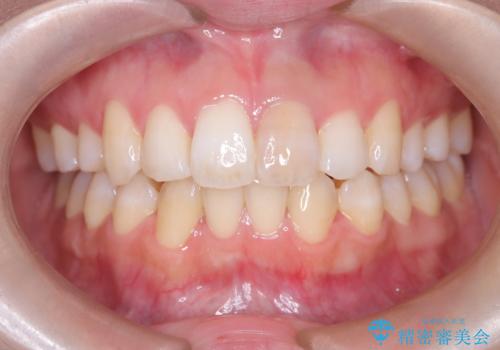

オールセラミッククラウンによる修復: 最終的な被せ物には、一切の金属を使用しないオールセラミックを選択。隣の天然歯と色調や透明感を精密に合わせることで、どこを治療したかわからないほど自然な仕上がりとなりました。